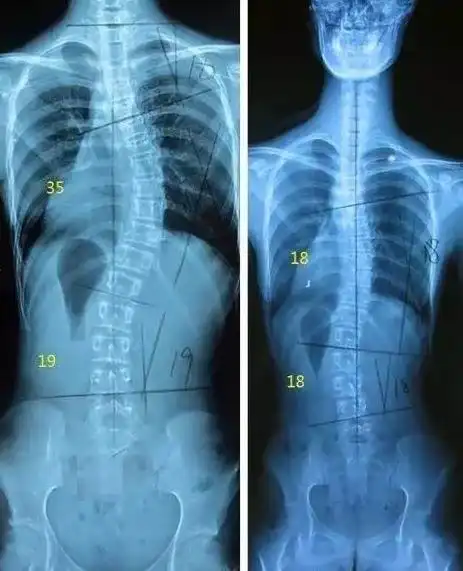

13岁少女肩膀一高一低!专家:当心青少年脊柱侧弯

听过吗?用3d打印辅助治好青少年特发性脊柱侧弯!

青少年特发性脊柱侧弯病例1 - 好大夫在线

儿童青少年脊柱侧弯不容忽视

青少年脊柱侧弯